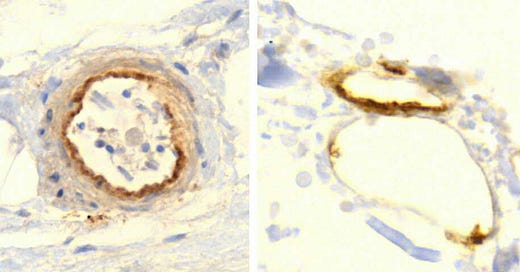

3. Expression of viral proteins can be detected with immunohistochemistry

While the distribution of the model vaccine leads us to expect widespread expression of the spike protein, we are here after solid proof. Such proof can be obtained using immunohistochemistry, which method is illustrated in this slide for the vaccine-encoded spike protein.

If a vaccine particle—composed of the spike-encoding mRNA, coated with lipids—enters a body cell, this will cause the spike protein to be synthesized within the cell and then taken to the cell surface. There, it can be recognized by a spike-specific antibody. After washing the tissue specimen to remove unbound antibody molecules, the bound ones can be detected with a secondary antibody that is coupled with some enzyme, often horseradish peroxidase. After another washing step, the specimen is incubated with a water-soluble precursor dye that is converted by the enzyme to an insoluble brown pigment. Each enzyme molecule can rapidly convert a large number of dye molecules, which greatly amplifies the signal.

At the top right of the image, you can see two cells which were exposed to the Pfizer vaccine and then subjected to the protocol outlined above. The intense brown stain indicates that the cells were indeed producing the spike protein.

In short, wherever the brown pigment is deposited, the original antigen—in this example, the spike protein—must have been present. Immunohistochemistry is widely used not only in clinical pathology but also in research; it could readily have been used to detect widespread expression of spike protein in animal trials during preclinical development. However, it appears that the FDA and other regulators never received or demanded such experimental data [6].

8. Expression of spike protein within the walls of small blood vessels

We see spike protein expression in arterioles (small arteries; left) as well as in venules (small veins) and capillaries (right). Expression is most prominent in the innermost cell layer, the endothelium. This makes the endothelial cells “sitting ducks” for an attack by the immune system.